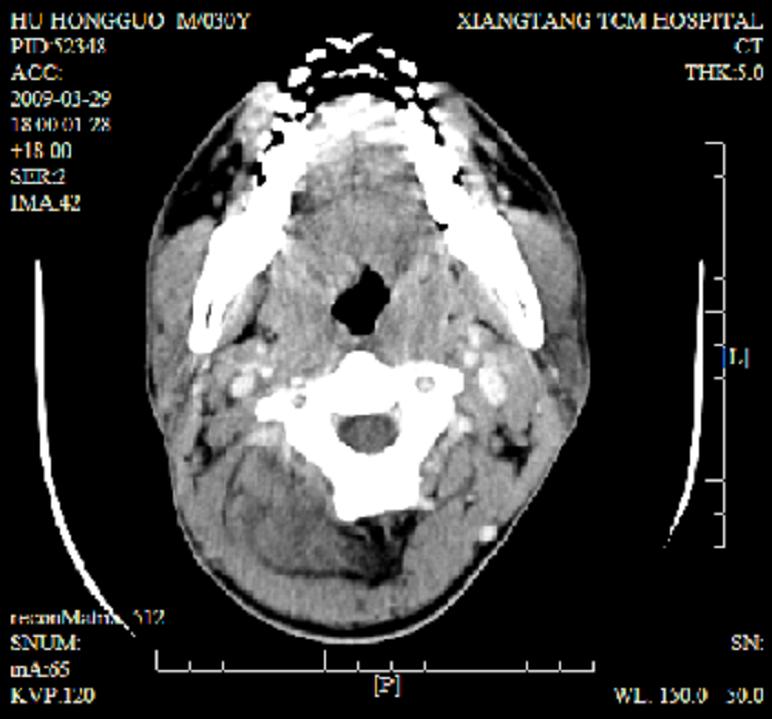

标题: CT19102:颈部肿块

男30y发现肿块3年

多处囊实性肿块,形态欠规则有一定形态,内见点状钙化,以囊变为主,增强后轻度强化,首先考虑神经源性肿瘤如鞘瘤,不除外脉管源性肿瘤如淋巴管瘤(见缝钻及囊性区域太多,如果合并感染完全可以这个影像表现),和海绵状血管瘤,但是血管瘤不太支持因为强化特征和病灶形态不典型.

右侧椎前间隙后部肌间、皮下囊性为主病变,可见分隔和点状钙化,分隔和壁呈轻度环形强化,大部分无强化。形态不规则,有钻缝特点。考虑1 淋巴管瘤合并感染2 血管平滑肌脂肪瘤3 表皮样囊肿4 不除外海绵状血管瘤。

病灶沿皮下及肌间隙爬行,病灶内有钙化灶,病灶有强化。病史3年,病人应该没什么症状。考虑纤维血管瘤可能性大。